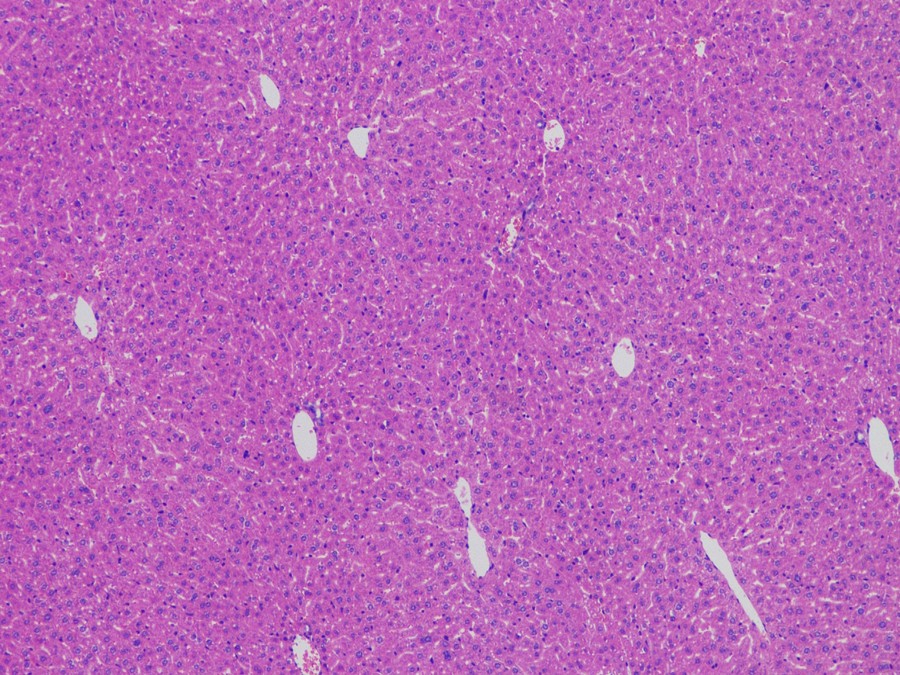

ML31下的正常肝細胞

肝臟主要由肝細胞組成,正常的肝臟HE染色切片在鏡下呈現(xiàn)為綿密的肝細胞,細胞核清晰可見且形狀比較規(guī)則,細胞間有少量不規(guī)則的空洞區(qū)域。